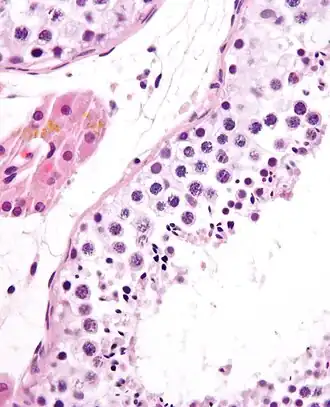

Um túbulo seminífero, com as células da linha germinativa. Coloração H&E.

A espermatogénese ocorre em várias estruturas do sistema reprodutor masculino. As etapas iniciais têm lugar nos testículos, passando depois para o epidídimo, onde os gâmetas em desenvolvimento sofrem maturação e são armazenados até à ejaculação. Os túbulos seminíferos dos testículos são o ponto de partida do processo, onde as células basais adjacentes à parede interior do túbulo se dividem numa orientação centrípeta—começando nas paredes e progredindo até ao lúmen—produzindo espermatozóides imaturos. A maturação tem lugar no epidídimo.